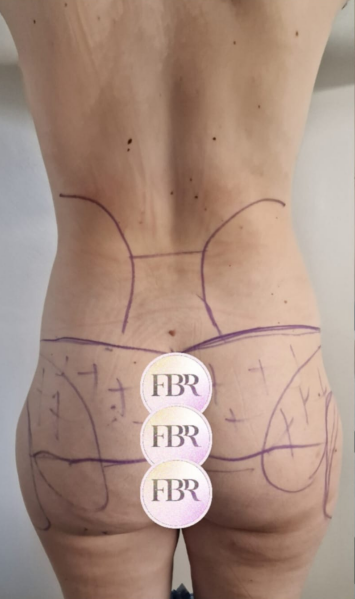

Découvrez les résultats de du lipofilling des fesses sur nos patients

AVANT

APRÈS

Autres résultats

Ces cartes sont cliquables : cliquez ou appuyez sur une carte pour ouvrir le cas en grand (même présentation AVANT / APRÈS que ci-dessus).